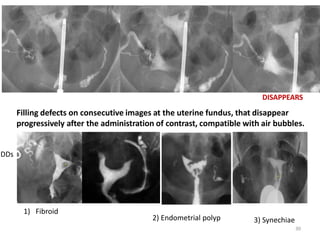

Filling defects on consecutive images at the uterine fundus, that disappear

progressively after the administration of contrast, compatible with air bubbles.

DISAPPEARS

DDs

1) Fibroid

2) Endometrial polyp 3) Synechiae